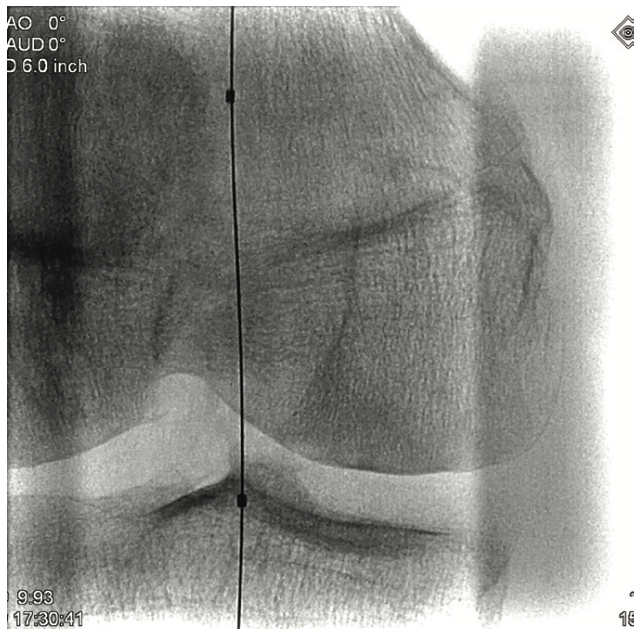

A 6 French (Fr) sheath was inserted into the right femoral artery in an antegrade fashion. An .035-inch x 90 cm Trailblazer (Medtronic) was inserted over an .035-inch x 180 cm Aquatrack guidewire (Cordis, A Cardinal Health company) and advanced into the right popliteal artery. Angiography was performed prior to surgical cut down of the posterior tibial artery (PT) (Figure 1). Access into the PT was made using a 4 Fr micropuncture pedal sheath (Cook Medical). An .014-inch Confianza guidewire (Asahi Intecc) was inserted and advanced into the PT. Using the stiff Confianza, a Viance Flexible CTO catheter (Medtronic) was advanced. When Viance extravasated from the PT, an Aquatrack wire and .035-inch Trailblazer were introduced and advanced in a antegrade manner. The Viance and Trailblazer could be visualized going in different directions (Figure 2). Using that image, the Viance was pulled back and repositioned to find the true lumen from the bottom to the top, using the guidance from the wire. The Confianza was readvanced after the true lumen was found, and Aquatrack was pulled back into the Trailblazer and eventually removed. The Confianza wire was advanced further into the .035-inch Trailblazer, and eventually pulled through the right femoral artery sheath in a retrograde fashion (Figure 3). The right femoral artery Trailblazer was removed. A TurboHawk SX-C atherectomy catheter (Medtronic) was used to debulk the plaque and achieve luminal gain from the popliteal artery into the tibioperoneal trunk (Figure 4). Drug-coated balloon angioplasty was performed using the IN.PACT balloon (Medtronic) into the popliteal artery (Figure 5). The TurboHawk was reinserted and advanced further down to the peroneal artery into the tibioperoneal trunk in order to establish luminal gain in the distal vessel. Final angiography revealed successful recanalization of the lower extremity vessels through the use of the antegrade/retrograde method, with distal access through the posterior tibial artery (Figure 6).